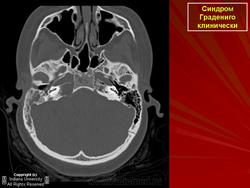

Диагноз петрозит ставят на основании анамнеза, в котором выявляется острое (или обострение хронического) гнойное воспаление среднего уха с явлениями мастоидита. Основным диагностическим критерием петрозита является триада Градениго и постепенное вовлечение в патологический процесс других близлежащих черепных нервов. Окончательный диагноз устанавливают после рентгенологического обследования (проекции Шюллера, Шоссе-III, аксиальная компьютерная томография).

В 1904 г. итальянский оториноларинголог G.Gradenigo (1859-1926) описал случай лептоменингита ушного происхождения, сопровождавшегося триадой симптомов - гнойным воспалением среднего уха, параличом отводящего нерва и болями в области иннервации тройничного нерва (синдром Градениго). Как выяснилось, этот редкий синдром обусловлен осложнением гнойного среднего отита, проявившимся остеитом и гнойным расплавлением каменистой части височной кости (петрозит).

Патогномоничен для этого синдром Градениго, однако, помимо отводящего нерва, в процесс могут вовлекаться лицевой, языкоглоточный и добавочный нервы. В целом, поражение указанных нервов обусловлено наличием локального менингита у верхушки пирамиды или повышением внутричерепного давления. Поражение тройничного нерва вызывает гемикранию, при этом может наблюдаться симптом Бруннера - понижение чувствительности роговицы на стороне поражения.